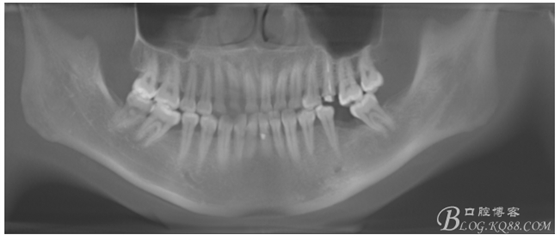

檢查:36.46缺失,36缺牙區(qū)近遠(yuǎn)中間隙約3mm,46缺牙區(qū)間隙約0.5mm,37.47.48近中傾斜,48近中面齲壞達(dá)牙本質(zhì)淺層,37牙周探診4mm,47近中探診深度5-6mm,不松,口內(nèi)照片及CT片如下:

術(shù)前CT